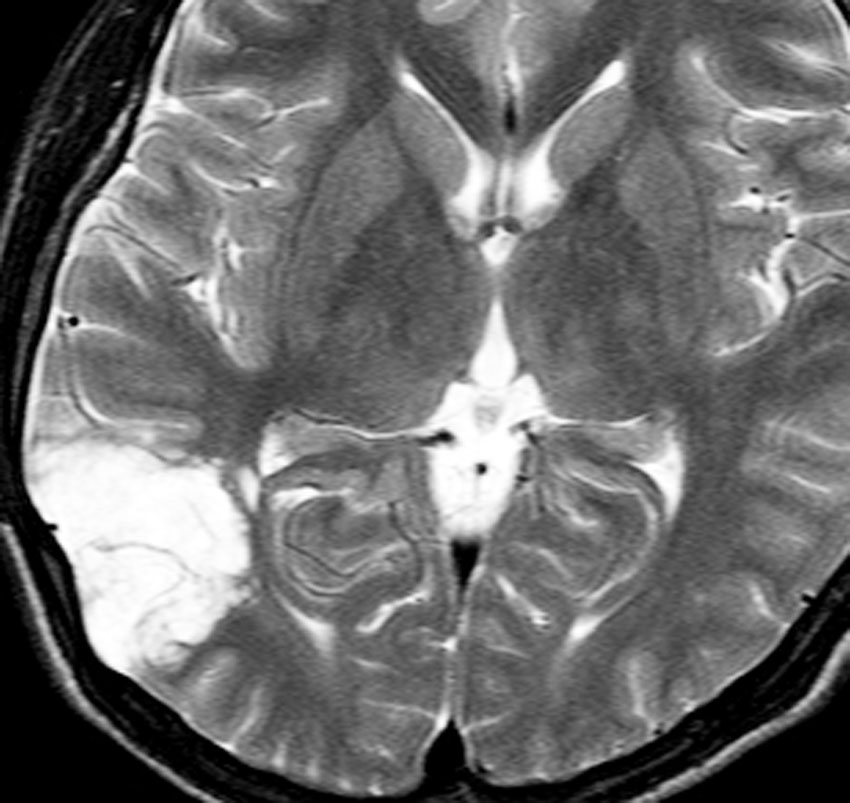

10代の少女に見つかったDNTです。難治性のてんかんがあり1日になんども意識減損を生じて,けいれんを止める薬をたくさん飲んでいて副作用のために眠気で日常生活が困難でした。でも,他の症状は何もありませんでした。左の頭頂葉と側頭葉と後頭葉の境目にできたものです。おそらくお母さんのお腹の中いたときからあった腫瘍なので何もしないで様子を見てもいいのです。でも,てんかん発作がひどいので腫瘍だけを摘出しました。DNTだけを取っても後遺症が残ることはほとんどありません。この場所は周囲の脳組織をとると後遺症がでる場所 (eroquent area)なので,てんかんを止める目的でもかなりの理由がないと周囲の脳組織は摘出しません。この子は,抗てんかん薬もいらなくなって完治しました。